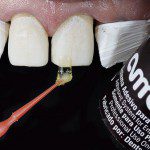

A figura 29 evidencia a aplicação do adesivo monocomponente (Ambar) sobre o esmalte e dentina com um Cavibrush. É importante salientar que o esmalte pode estar seco ou úmido, mas a área de dentina exposta, neste caso a cervical, deve ser previamente reidratada.

- Figura 29